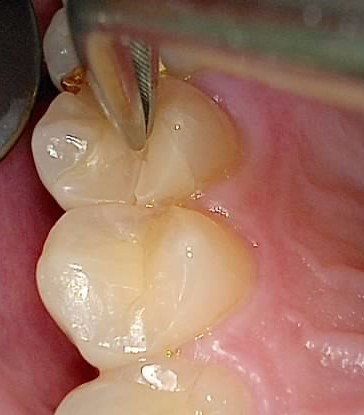

파절편과 기존 인레이를 제거한 결과

👉 치관의 절반이 파절, 뿌리 일부도 손상된 상태.

하지만 뿌리 길이가 길고, 치조골 상태가 양호하여

환자분과 상의 후, 자연치 보존 치료를 선택했습니다.

🦷 치료 과정 요약

- 신경치료 진행

- 기둥(포스트) 보강

- 임시치아 사용 후 통증 확인

- 최종 크라운 완성

👉 치료 후 식사에 문제 없었고, 결과에 만족해하셨습니다.

물론 예후가 임플란트보다 긴 보장은 어렵지만,

“자연치를 보존하고 싶다”는 강한 의지가 있는 분이라면

가능한 옵션입니다.